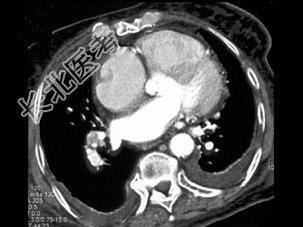

- 单项选择题男,38岁, 反复咳嗽、咳痰伴发热15年余,痰结核菌素试验(—), 结合CT图像,最可能的诊断是 ( )